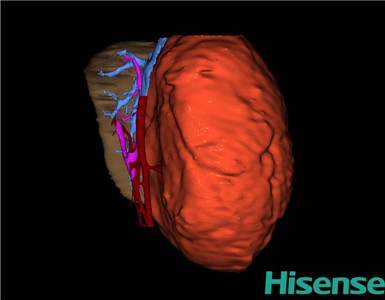

将0.625mm双源薄层CT资料的静脉期和动脉期Dicom格式文件导入海信CAS系统。

通过调节窗宽窗位调整CT序号,对肝实质,胆囊,下腔静脉,肿瘤,肝动脉、门静脉及肝静脉等进行三维重建;系统自动计算肝脏体积。

模拟手术操作,自动计算切除肝体积、肿瘤体积、剩余功能性肝体积。

肝脏体积为218.1ml,肿瘤体积为1570ml,肿瘤体积为肝脏体积的7.2倍,通过比对1-3月正常肝脏体积为174.85±58.11ml,通过术前模拟手术,精准判断切除后剩余肝脏体积能耐受,避免肝衰竭发生。

术前三维重建:

重建图片